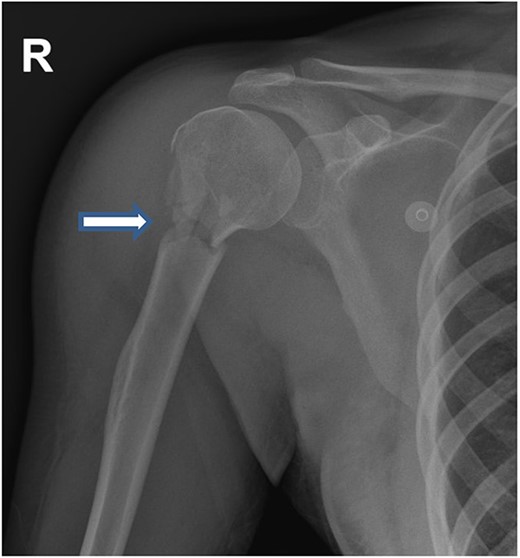

In total, 11 units of RBC, 12 units of fresh frozen plasma and 12 units of platelet concentrate, 6 units cryoprecipitate, Prothrombin complex concentrate (1000 units), fibrinogen (12 gram) and tranexamic acid were transfused (ROTEM-guided). The patient also received oxytocin (40 units) and methergine (0.4 mg) injections for the prevention and control of postpartum hemorrhage and then transferred to the hybrid operating room for imaging. Computed tomography (CT) scan revealed small laceration in the right lobe of the liver (segment 8) and another laceration at the upper pole of the right kidney without active bleeding. However, there was a focus of contrast blush seen in the arterial phase at the right lateral side of the uterine wall, which increased in the venous and delayed phases suggesting active arterial bleeding (Fig. 1a–c). The contrast extravasation is also seen within the endometrial cavity (Fig. 1c). Interventional radiologist was consulted, and he advised for close observation because these findings could be related to immediate postpartum uterine changes. The patient was transferred to the Trauma Intensive Care Unit (TICU) under mechanical ventilation, where she was hemodynamically stable. The last Intra-operative lab work showed hemoglobin level of 10 g and base excess was improved from −16 to −9 mEq/l. For completion of secondary survey, right shoulder X-ray was done and revealed a fracture of the right humerus head (Fig. 2). Few hours after admission to the TICU, the patient had post partum hemorrhage as frequent changing of blood-soaked packs was required and the hemoglobin dropped from 10 to 7 g. Sweeping of the uterine cavity was done by the obstetrician and small pieces of membranes was removed and no placental tissue was felt. Oxytocin drip 20 units in 500 ml was given intravenously and misoprostol 600 mcg was given rectally.

On the second day, the patient had normal coagulation parameters, stable hemoglobin level and her acidosis resolved. She was taken back to the operating room where the packs were removed and no active bleeding was noted, the abdomen was closed, and the patient was transferred back to the TICU. She was extubated and had uneventful recovery. The patient was transferred to the trauma ward on the third hospital day. Her humerus fracture was evaluated by orthopedic team and treated conservatively.